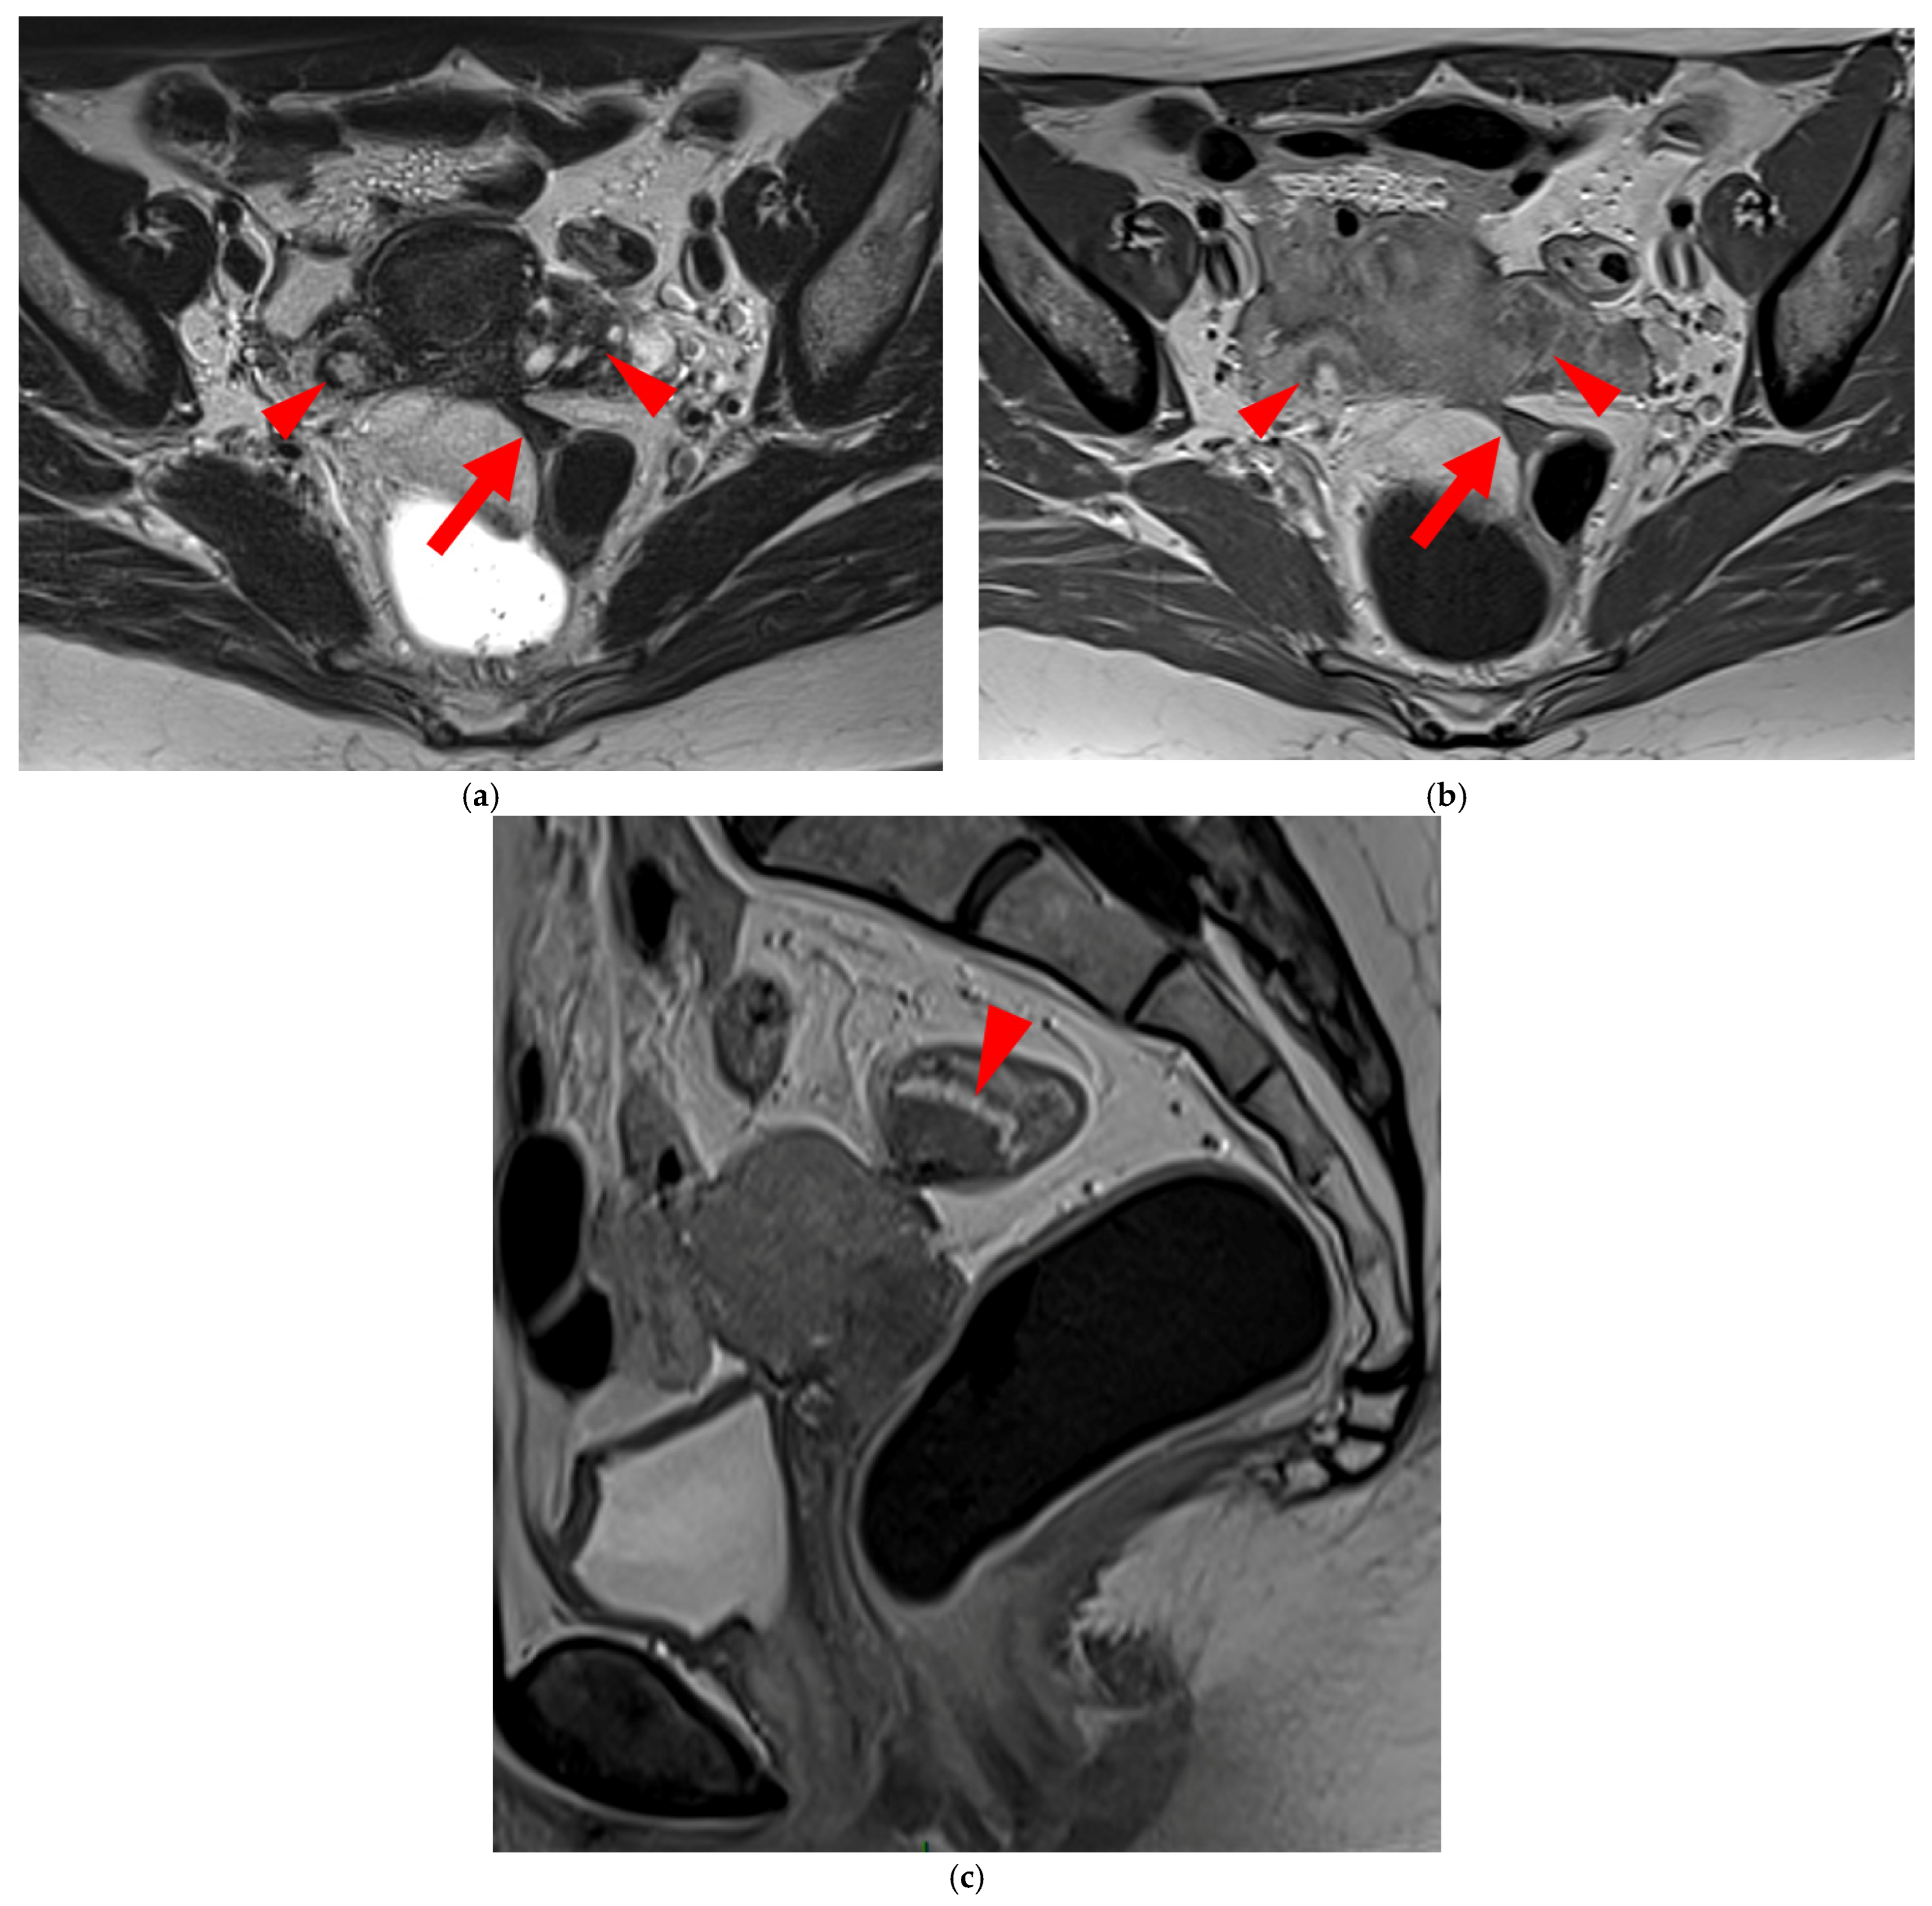

Diagnostics 15 01508 g003

Figure 3. Pelvic MRI scans of three patients with thick (>2 mm), smooth, and regular USLs (HTD type 3A). (a) Sagittal T2WI: a thick (2.8 mm), smooth, tapering-shaped left USL (arrowhead). (b) Axial T2WI: regularly thickened (3 mm) right USL with a smooth surface (arrowhead). (c) Axial T2WI: regularly thickened (4.1 mm) right USL with a smooth surface (arrowheads).

Diagnostics 15 01508 g004aDiagnostics 15 01508 g004b

Figure 4. Pelvic MRI scans of seven patients with HTD type 3B USLs. (a) Sagittal T2WI: a thickened (2.1 mm) and stiffened right USL (arrowhead) with “bowstringing”. (b) Axial T2WI: a caliber disparity (dashed arrows) with focal thickening (4.2 mm) of the left proximal USL (arrowhead). (c) Sagittal T2WI: a caliber disparity (dashed arrows) with focal thickening (2.5 mm) of the right distal USL. (d) Axial T2WI: a right USL with a notched and irregular surface (dashed arrows). (e) Axial T2WI: thickened and stiffened left (3 mm) and right (2.5 mm) USLs with “bowstringing” of both USLs (arrowheads). (f) Sagittal T2WI: a thickened (2.6 mm) right USL with a stiffened appearance characterized by a steep vertical orientation (arrowhead). (g) Sagittal T2WI: the right USL appears thin (1.9 mm) but stiffened (arrowhead), exhibiting “bowstringing”. These findings led to its reclassification from type 2 to type 3B.

A type 3A USL (Figure 3) maintains a smooth appearance with regular margins and often retains a tapering shape despite its thickening.

A type 3B USL (Figure 4), in addition to being thickened, has a notched surface with slightly irregular margins, or a caliber disparity with focal thickening, or appears “stiffened”, which means it loses its curvilinearity to exhibit a steep vertical orientation in the sagittal plane or a “bowstringing” of the USL in the sagittal or axial planes. Occasionally, a USL might appear thin but “stiffened”, which would upgrade it from a type 2 to a type 3B.